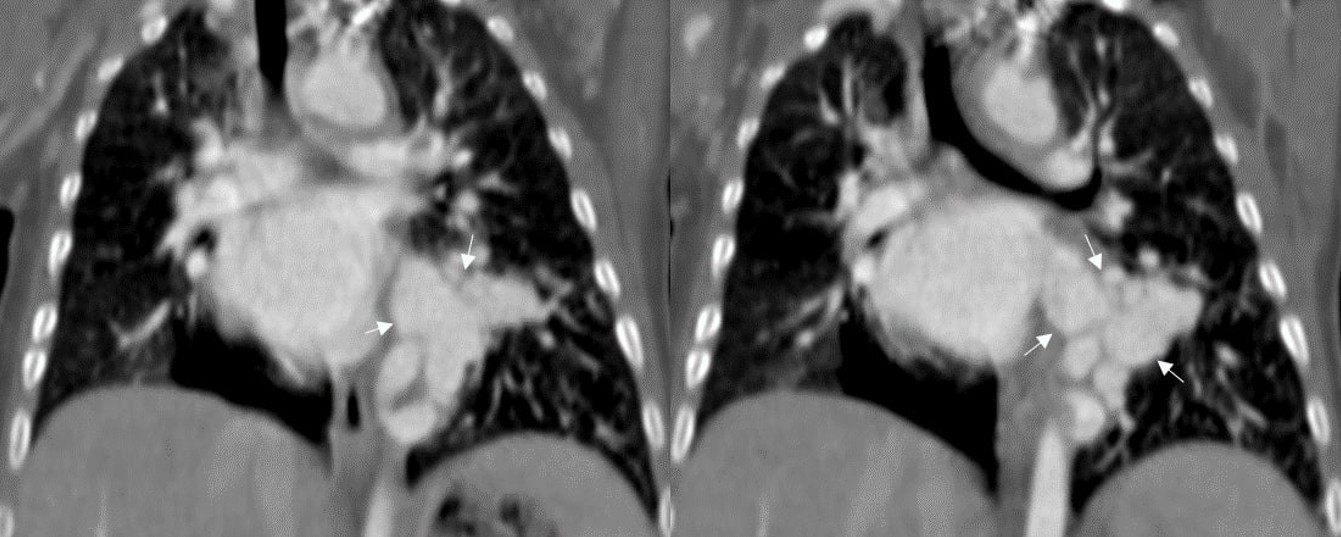

A 5-month-old infant was referred to our hospital after a suspected cardiac murmur was detected during a routine health check-up. Born via cesarean section at 39 weeks, the patient had no history of neonatal hospitalization, respiratory distress, or episodes of infection or bronchiolitis. Routine laboratory tests, including a complete blood count and assessments of kidney and liver function, were all normal. Chest X-ray revealed ground-glass opacities in the left upper and middle lung zones and opacification in the left lower zone (Figure 1). Thoracic CT and CT angiography were performed for further evaluation, with CT angiography demonstrating an aberrant vessel originating from the supradiaphragmatic descending aorta (Figure 2). This large systemic artery had three branches supplying the left lower lobe. Venous drainage from the affected lung parenchyma occurred via a dilated, tortuous left inferior pulmonary vein into the left atrium (Figure 3). No parenchymal abnormalities were observed, and the left lower lobe bronchus and its segmental branches appeared normal. These findings supported a diagnosis of pseudosequestration, as the affected lobe maintained a connection with the bronchial tree, differentiating it from true sequestration.